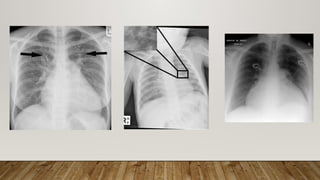

CHEST X-RAY

• Focal alveolar or interstitial infiltrate

• Pulmonary edema

• Bilateral cephalization of the pulmonary vasculature

• Peri-bronchial cuffing

• septal thickening,

• intralobular thickening

• widened mediastinum raises the possibility of a pericardial effusion.

Focal oligemia

West mark sign

Hamptons Hump Palla’s sign